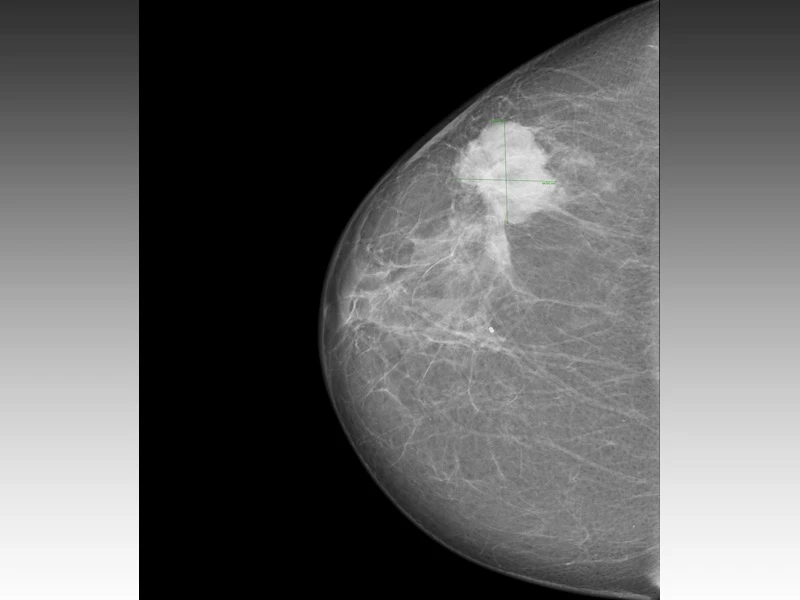

Você sabe onde encontrar uma mastologia para doenças graves Alto de Pinheiros? As doenças da mama merecem atenção especial, principalmente quando nos referimos ao tema de maior medo entre as mulheres: o câncer de mama. Nossa clínica oferece tratamento para as doenças benignas da mama (cistos, nódulos, dor mamária, ginecomastia, entre outras), doenças malignas da mama (câncer), além de biópsias e cirurgias mamárias.

A Clínica Bem Estar é composta por médicos especialistas em Mastologia, Ginecologia e Obstetrícia, Cirurgias Ginecológicas e Mamárias, Modulação Hormonal, Oncologia Pélvica e Reprodução Humana. Quando o assunto envolve doenças benignas e malignas da mama, a nossa clínica contém toda a estrutura necessária para realização de tratamentos personalizados para as nossas pacientes.